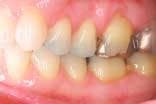

The assistant retracts the lips for the next set of images. These two images are the arches in occlusion and slightly open. The image of the teeth in occlusion gives us information on overbite, overjet, cross bites, gingival recession, Golden Proportion, Shimbashi number, and exostosis. A periodontal probe can be placed on the central incisor as a reference for measurement. This view can be used to analyze and diagnose Golden Proportion on a printed view with a ruler and pen or with measurement tools found in many software applications.

The final two shots are the left and right buccal shots in occlusion. This view highlights gingival contour, recession, and the occlusal relationship of the upper and lower teeth.